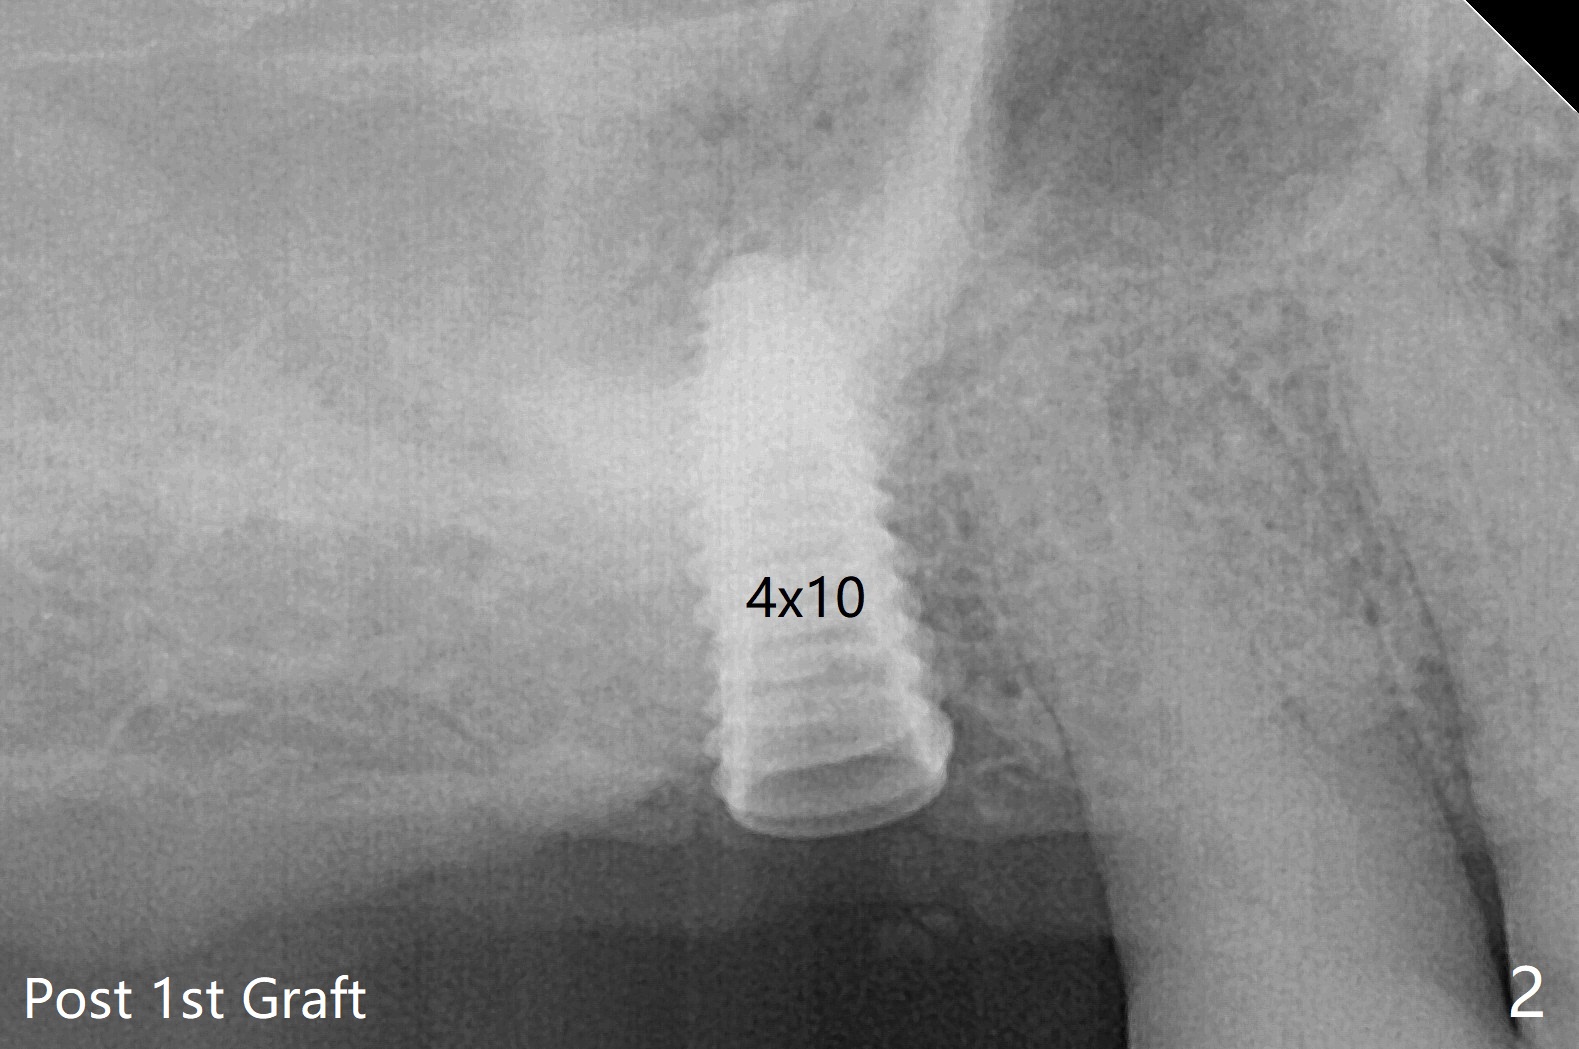

在导板协助下,顺利完成右上6钻洞,用圆钻穿过上颌窦底板,然后使用粘性骨粉(之前半张PRF膜)和4乘10毫米报废植体做第一次(图一,二),第二次(图三),第三次(图四,五)提升,退出报废植体后,拧入正式植体(4.5乘8.5毫米)。由于扭力大约10Ncm,放置愈合螺帽。植体颊侧骨壁比较低,螺帽上放置骨粉(图四,五:*),后者太多,再没有空间放置PRF膜,只好放置在骨粉表面,容易滑动,所以需要安置间隙保持器(图四,五)。在拍摄根尖片时,PRF膜丢失,只好在骨粉表面放置Teflon,然后放置牙周敷料,借助保持器固定。术后两周牙周敷料脱落,而间隙保持器仍在,下面牙龈基本愈合(图六,7)。今后使用导板做上颌窦提升,种植,最好使用导板的环形刀在牙龈上轻轻做过标记,然后用Biopsy Punch完整切除牙龈,放置于PRF上清液备用。如果植体扭力低,放置骨粉后,覆盖切除的牙龈,牙周胶水固定。